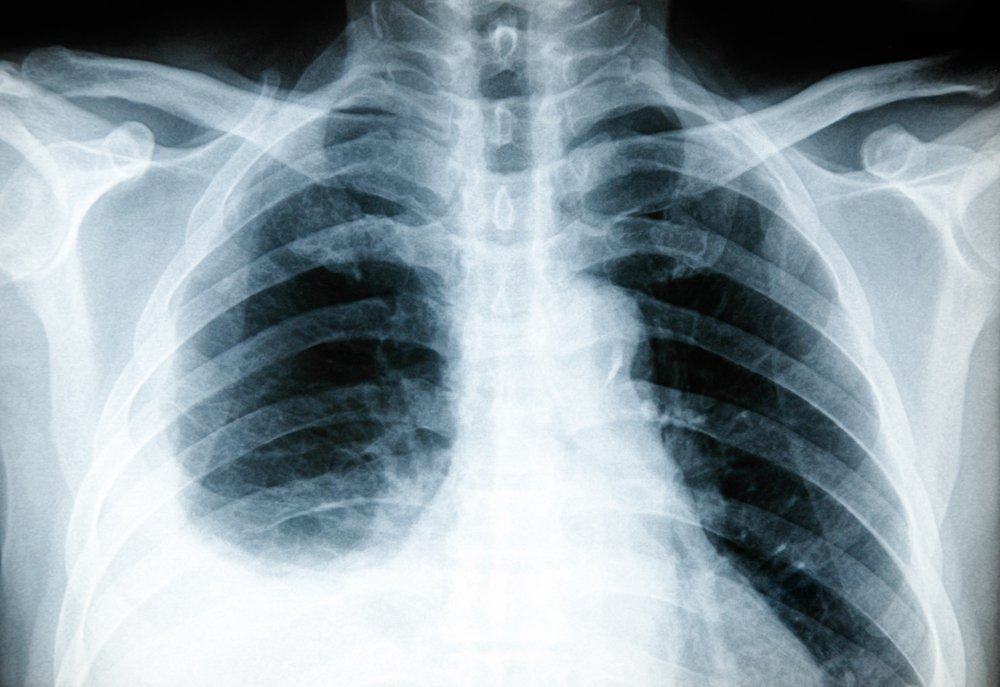

Tes x-ray di bagian dada dapat membantu dokter mengetahui adanya peradangan pada paru-paru Anda. Jenis x-ray yang dilakukan adalah dekubitus, yaitu x-ray yang diambil ketika Anda berbaring dengan posisi miring.

Dengan posisi ini, penumpukan cairan yang terdapat di pleura Anda dapat terlihat secara lebih jelas.